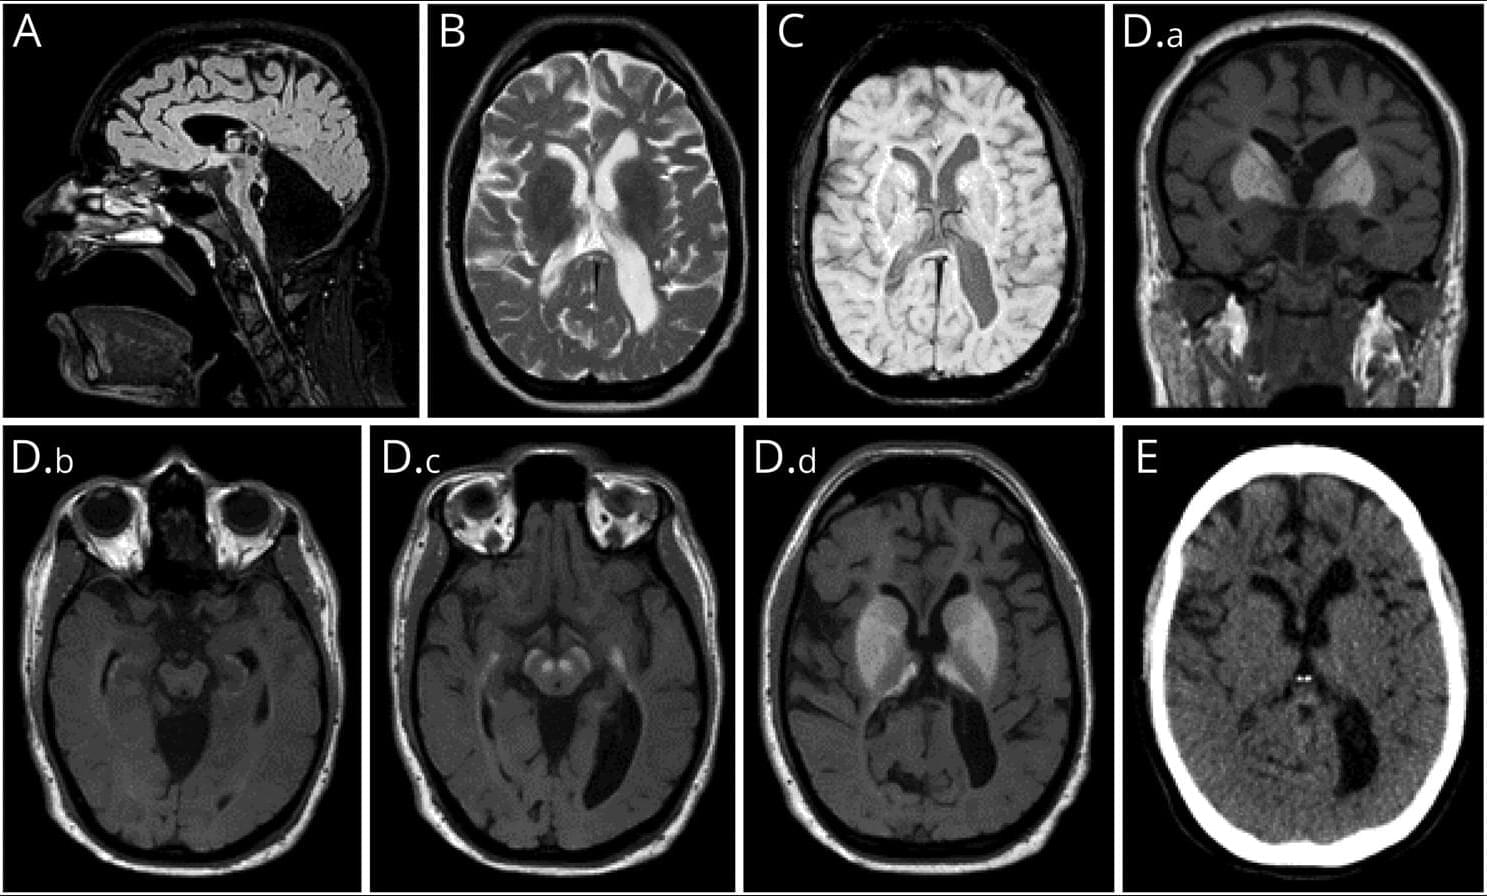

Central vein sign and paramagnetic rim lesions can aid in an earlier diagnosis of late-onset multiple sclerosis and may circumvent the need for biopsy. Learn more in this Pearls & Oy-sters article.

Owing to concerns for neurosarcoidosis, lymphoma, or vasculitis, a percutaneous stereotactic biopsy of a right occipital lesion was performed. Pathology revealed a demarcated CD68/163+ macrophage-rich lesion with myelin loss, relative axonal preservation, and a CD3+ predominant lymphocytic infiltrate with rare CD20+ B cells, consistent with active demyelination (Figure 2). She initiated a 5-day course of high-dose oral prednisone (1,250 mg daily) followed by a taper. Within 2 days of treatment, she experienced mild improvement in dysarthria and ataxia, although her EDSS score remained 6 on discharge.

Open in Viewer.